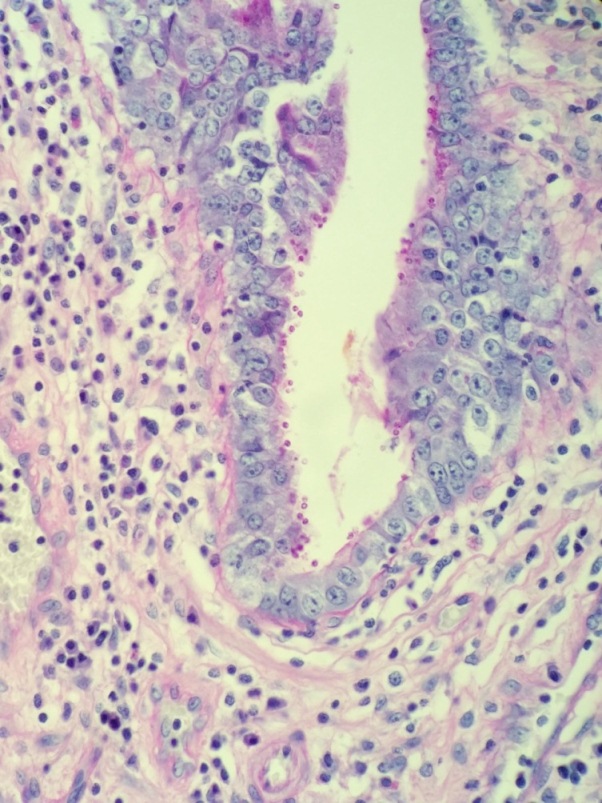

A 52-year-old male with HIV presents with profuse, watery diarrhea of 5 days’ duration. A biopsy of the small intestine is shown here. What is the most likely cause of this patient’s symptoms?

Explanation: ***Cryptosporidium spp.*** - The image shows numerous **small, round, purple-stained organisms** adhering to the brush border of intestinal epithelial cells, which are characteristic of *Cryptosporidium* oocysts. - In an **HIV-positive patient** with profuse, watery diarrhea, *Cryptosporidium* is a common opportunistic infection that can cause severe and prolonged symptoms, especially when CD4 count is <200 cells/μL. - Diagnosis is confirmed by identifying **acid-fast oocysts** (3-6 μm) attached to the intestinal epithelial surface. *Giardia lamblia* - *Giardia* typically presents as pear-shaped **trophozoites** with flagella or oval **cysts** in the intestinal lumen, which are much larger (10-20 μm) than the organisms seen in this biopsy. - While *Giardia* can cause diarrhea in immunocompromised individuals, the morphology and location (attached to brush border vs. free in lumen) do not match. *Cystoisospora belli* - *Cystoisospora* (formerly *Isospora belli*) is another important cause of chronic diarrhea in HIV patients but appears as **large, elongated oocysts** (20-30 μm) that are acid-fast positive. - The organisms are typically found **within enterocytes** or in the lumen, not as small spherical structures on the brush border surface as seen here. *Cyclospora cayetanensis* - *Cyclospora* causes watery diarrhea in immunocompromised patients and appears as **round oocysts** (8-10 μm), larger than *Cryptosporidium*. - The oocysts are typically found in the **intestinal lumen** and stain variably with acid-fast staining, but the small size and surface attachment pattern in this image are more consistent with *Cryptosporidium*.